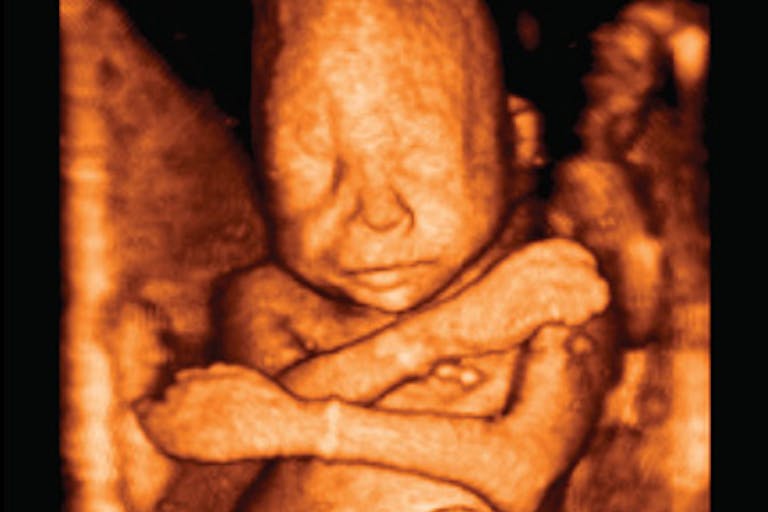

And so, for anyone involved in the abortion debate – and for all those who are unsure exactly where they stand – here are five important videos. These short videos show just what that unborn baby in his mother’s womb looks like, at various stages of development. Modern scientific videos like these demonstrate that unborn babies are not:

Rather than showing what abortion does to babies (you can see that here and here), these five videos demonstrate the reality and beauty of human life. Human life isn’t only beautiful after birth. Human life is beautiful – and worth valuing – at every stage. At the moment of fertilization, a new, unique human being comes into existence. She has her own unique DNA sequence that is present at that very moment. All she needs is a chance to grow and develop.

3. Watch your baby grow! Week by week ultrasounds

5. A 4D ultrasound journey from 8-34 weeks in the womb